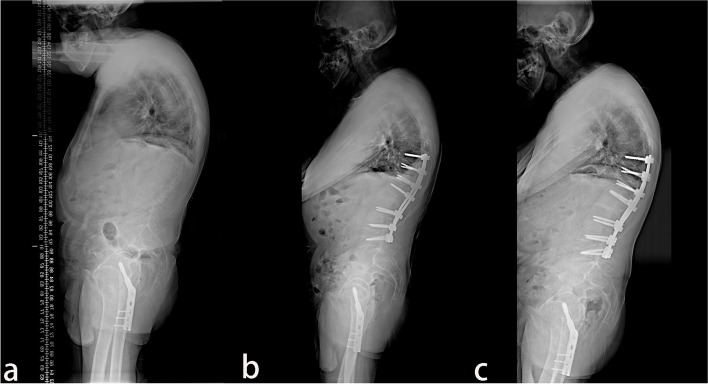

A total of 38 patients with AS combined with thoracolumbar kyphosis were successfully treated by PSO, with a mean follow-up time of 26.9 ± 11.9 months. There were 30 males and 8 females with a mean age of 41.6 ± 7.1 years. Twenty patients consisted in the lumbar lordosis group and 18 patients in the lumbar kyphosis group, with a mean operation time of 289.4 ± 123.2 min and 267.8 ± 96.8 min (P > 0.05), respectively. The patients were further subdivided into the lumbar lordosis T12 group (Fig. 1) with 11 patients, the lumbar lordosis L1 group (Fig. 2) with 9 patients, the lumbar kyphosis L2 group (Fig. 3) with 10 patients, and the lumbar kyphosis L3 group (Fig. 4) with 8 patients.

Fig. 2.

A 49-year old male patient with AS. a The preoperative X-ray showed that the parietal vertebrae were located at L2, which belonged to the lumbar lordosis group. b Single-segment pedicle subtraction osteotomy (PSO) was conducted at L1. Lumbar lordosis, global kyphosis, and sagittal vertical axis improved from the preoperative –25°, 79°, and 104.21 mm to –53°, 61°, and 30.34 mm, respectively. c At the last follow-up in the 30th-month post-operation, no apparent orthopedic loss was observed, and lumbar lordosis, global kyphosis, and sagittal vertical axis were –49°, 51°, and 31.76 mm, respectively